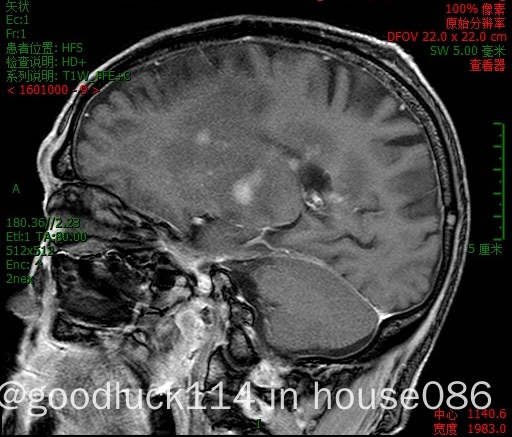

高龄取不了病理,医院做不了pet-ct,做了头颅ct和mri,发现颅内占位性病变,怀疑原发或转移,但胸部ct腹部ct和肿瘤标志物都没有明显异常,也没有除神经系统外其他系统的症状,mri增强结果不像是胶质瘤,高度怀疑是原发性中枢淋巴瘤。